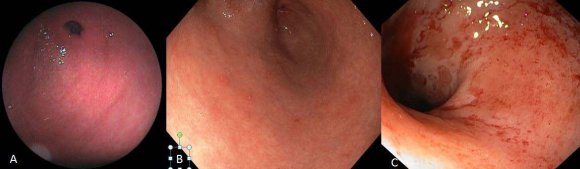

Ultrasound findings of gastritis were confirmed on gastros cop y examination (Figure7).

A penetrating Ulcer may extend up to Serosa, in cases of impending perforations. Hence all five layers are involved. 3 Gastritis can be acute and chronic. Acute gastritis can be mild and severe. In mild Acute Gastritis, the surface epithelium is intact. The mucosa is hyperaemic, oedematous, congested and red. Histologically, there are intraepithelial and intraluminal neutrophils. In severe acute gastritis, there are mucosal erosions with resultant loss of surface epithelium, hemorrhages seen as punctate dark spots with inflammatory and fibrino us purulent exudates. Acute erosive hemorrhagic gastritis is characterized by concurrent erosion and hemorrhages with extensive mucosal damage and is commonly seen in alcoholic and NSAID users. 4,5 Acute gastritis is caused by H. Pylori, other infectious causes (like bacteria, viruses, fungi and parasites), and non-infective gastritis. Chronic gastritis can be Type A (AutoImmune-Body-fundic predominant), Type B (H. Pylori related-Antral predominant), Type AB (Environmental-Antral-body predominant), Chemical (Reflux-Antral-body predominant) and uncommon forms of gastritis. [6][7][8] In Patients of Mild Acute Gastritis, there is a thickening of layer 2 and total gastric wall thickness, on ultrasound. The ratio of the thickness of Layer 2 to total Gastric wall thickness is significant. 9 Our observations indicate that transabdominal Ultrasound with Convex Probe, followed by Linear Probe, can predict diagnosis of Mild Gastritis and can reduce the number of Endoscopic Evaluations and further Ulcer formations. It can predict associated mucosal erosions if Layer 1 thickness is less than 1 mm with associated thickening of layer 2. In our case series, 5 cases of gastric erosions were detected on Ultrasound and were confirmed on gastroscopy.